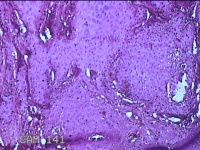

头部肿物

性别

男

年龄

21岁

临床诊断

头皮肿物

一般病史

发现头部结节10余年,无明显疼痛及不适。

标本名称

头部结节

大体所见

灰白暗红色带皮肤样结节1.5x1.3x0.3cm一个,切开结节呈实性,切面灰白粉红色,质软。